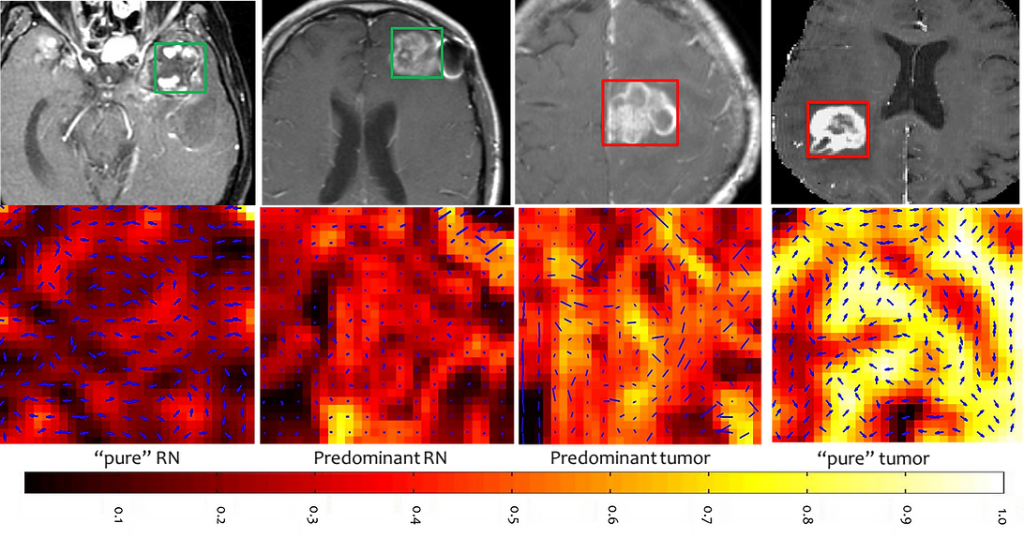

DIAGNOSTIC MODELING: Diagnosis of true-progression from treatment effects in brain tumors

One of the most challenging problems in management of cancer patients (especially in brain tumors) is to distinguish pseudo-progression or radiation necrosis (benign conditions caused due to radiation), affecting 20-40% of all brain tumor patients, from recurrent brain tumors (true progression). Currently, invasive biopsy offers the only reliable diagnosis, since these treatment effects and true progression have a similar visual appearance on routine MRI. We have developed a computerized decision support software toolkit, NeuroRadVisionTM, employing novel radiomic tools that in conjunction with multi-parametric-MRI enable discrimination of true progression from benign treatment effects. NeuroRadVisionTM has so far yielded 89% accuracy, while currently the diagnostic accuracy via visual inspection by radiologists (standard-of-care) on MRI is only 50-65% at best.